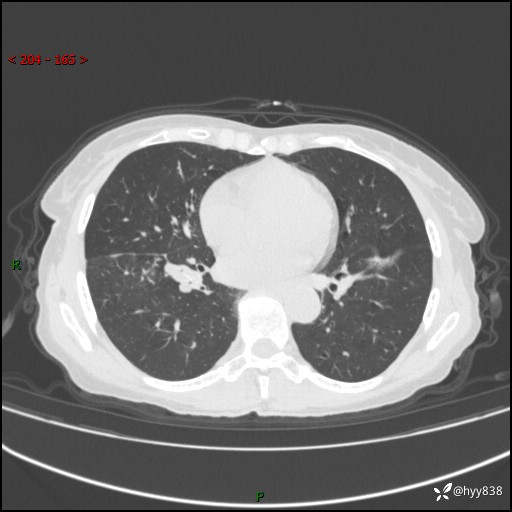

患者性别:男

患者年龄:69岁

简要病史:咳嗽咳痰2月,夜间加重

临床诊断:感染

胸部CT平扫